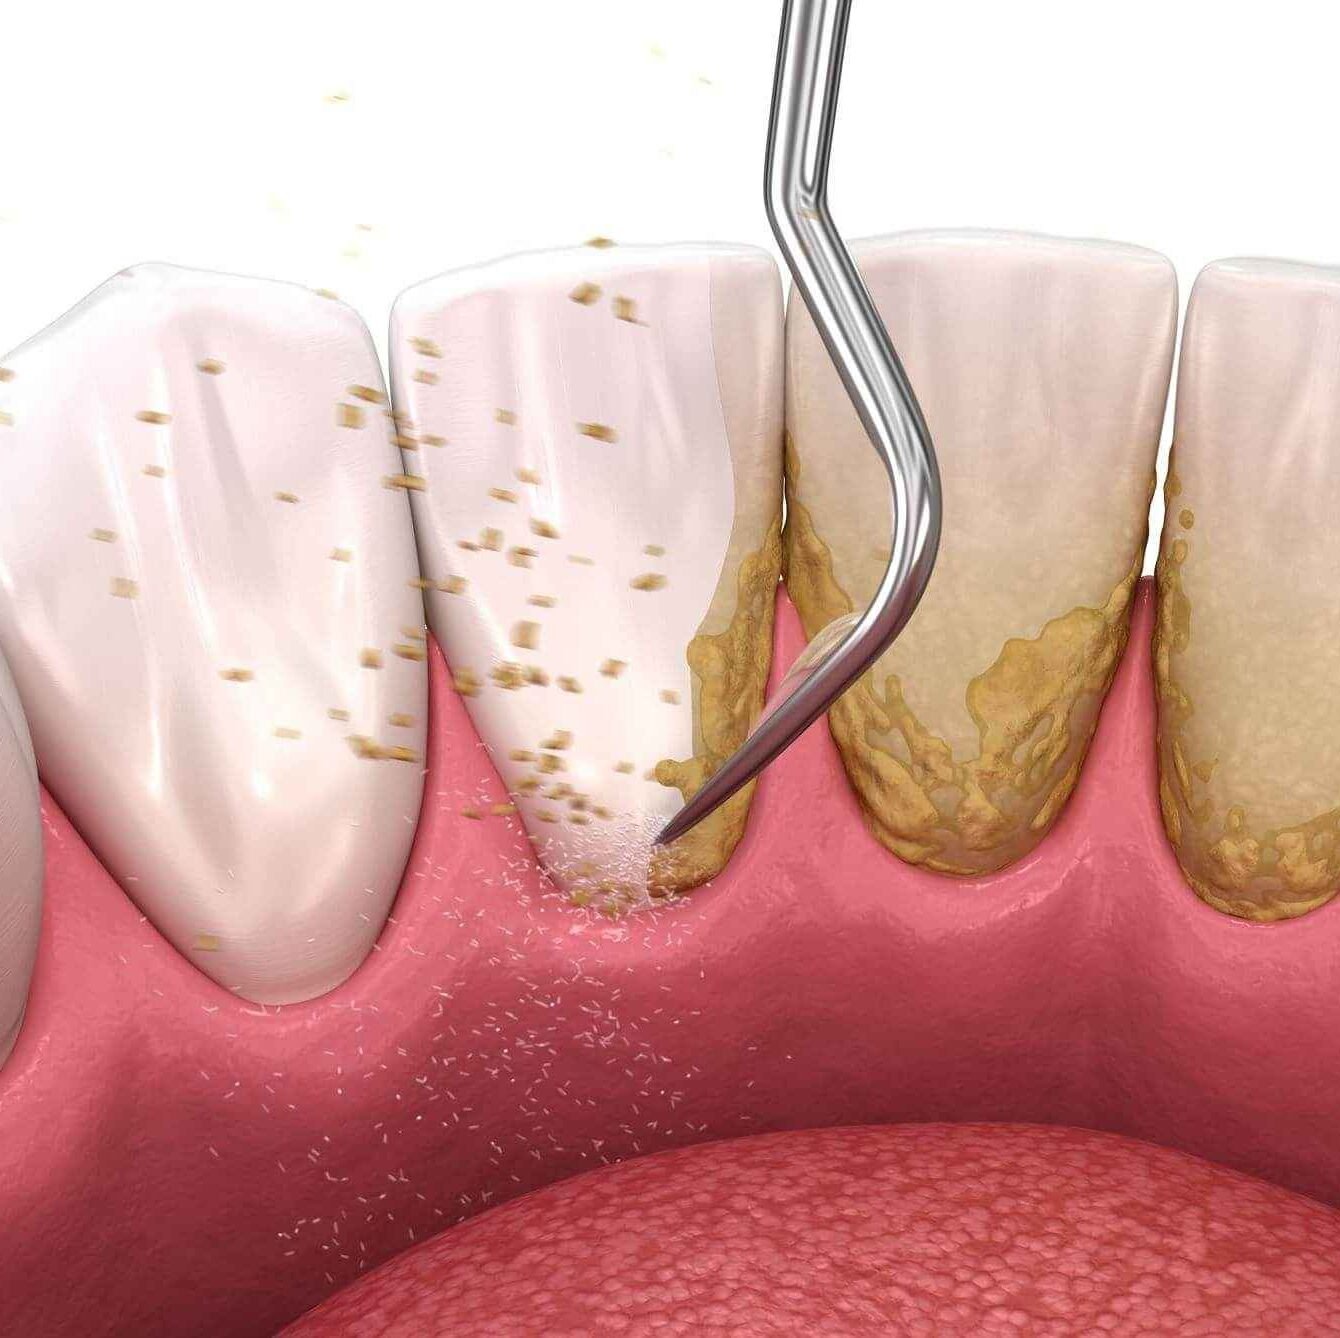

Prosedur pembersihan plak dan karang gigi untuk menjaga kesehatan gusi dan gigi.